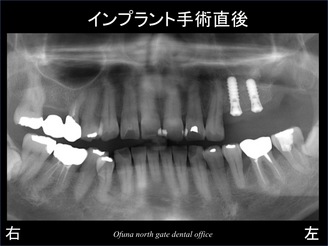

抜歯後、インプラント手術が終了した直後が以下のレントゲンです。

埋入した2本のインプラントの奥には、大きな穴が開いています。